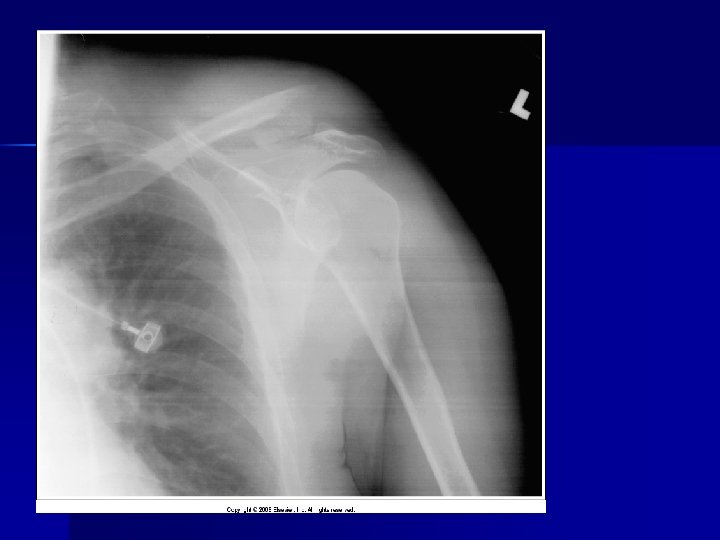

Evaluating Images What do you think?

n n n Does this show good detail? Is all of the anatomy present? How is the density / contrast?